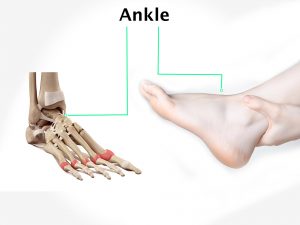

Skin receptors report a painful stimulus by sending electrical messages along sensory nerve fibers to the spinal cord. From there they travel to the brain, where the signals are interpreted as the sensation of pain. Sometimes you can feel pain in one part of the body even though the area affected is actually elsewhere. This is called referred pain, and one example is angina pain originating from oxygen starvation of the heart muscle but felt in the upper arm, shoulder and neck.